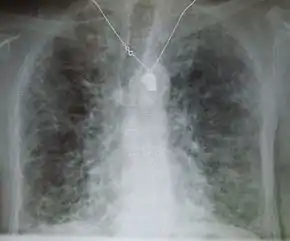

Chest radiography is usually the first test to detect interstitial lung diseases, but the chest radiograph can be normal in up to 10% of patients, especially early in the disease process.[13][14]

High-resolution CT of the chest is the preferred modality and differs from routine CT of the chest. Conventional (regular) CT chest examines 7–10 mm slices obtained at 10 mm intervals; high resolution CT examines 1–1.5 mm slices at 10 mm intervals using a high-spatial-frequency reconstruction algorithm. The HRCT therefore provides approximately 10 times more resolution than the conventional CT chest, allowing the HRCT to elicit details that cannot otherwise be visualized.[13][15]

Radiologic appearance alone, however, is not adequate and should be interpreted in the clinical context, keeping in mind the temporal profile of the disease process.[13]

Interstitial lung diseases can be classified according to radiologic patterns.[13]